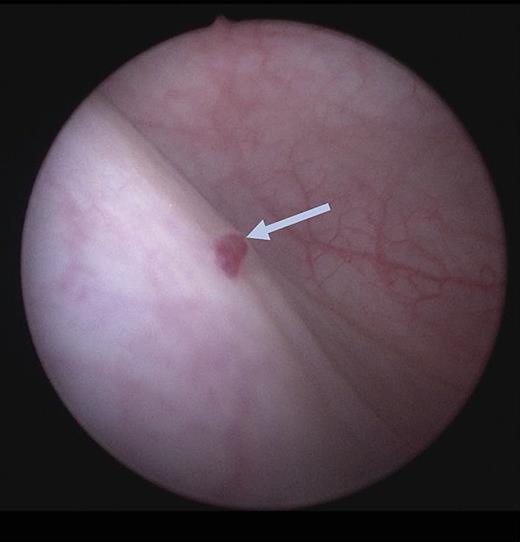

Cystoscopic findings of a sessile, blue, multilocular mass are strongly suggestive of a hemangioma [6]. Hemangiomas of the bladder range in diameter from a few millimeters up to 10 cm [2]. Most tumors are solitary, small (<3 cm), and have a smooth or irregular surface [2, 6], shown in Figure 1. The tumors usually involve the bladder dome, posterior wall, and trigone [6]. These lesions are pink to blue in color, soft in consistency, irregular in shape, and bleed easily on touch [4].